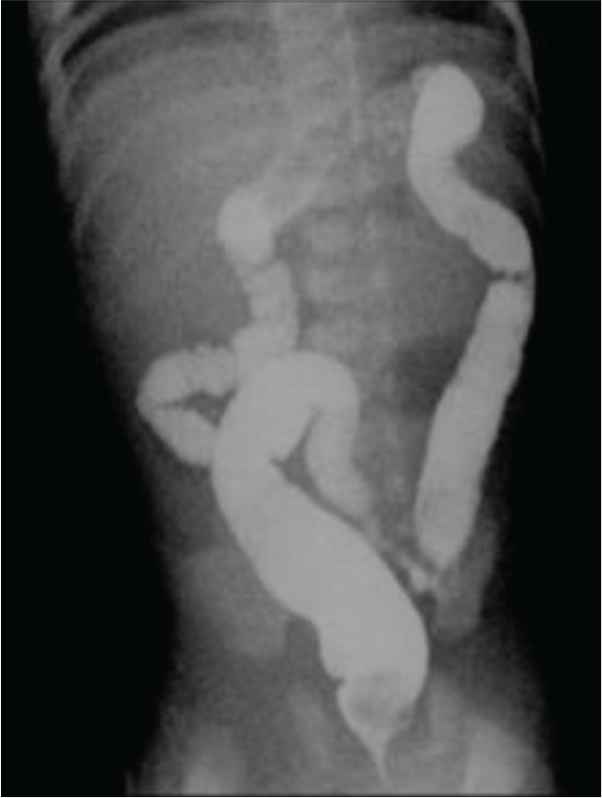

A full-term male with an unremarkable antenatal and perinatal history admitted on the date of birth to the Neonatal Intensive Care Unit (NICU) because of transient tachypnea of the newborn. During his stay, he developed episodes of hypoglycemia and intermittent yellow to green vomiting. There were no significant findings in the abdominal Ultrasound (US) and X-ray. He was discharged against medical advice as requested by the mother on the 3rd day of life. The baby stayed at home for 4 days with a history of intermittent vomiting. He was later readmitted to the NICU because of recurrent bilious vomiting and clinical jaundice on the 7th day of life. During his stay, he developed episodes of hypoglycemia and received phototherapy for prolonged jaundice and was kept Nill per oral (NPO) initially. Trials to resume feeding were always associated with intermittent vomiting, which was sometimes bilious or fecal. The result of abdominal examination was unremarkable. Interestingly, there was no distension, and the baby passed stool frequently. All workup to rule out sepsis, including metabolic disorders, were benign. Moreover, imaging studies, including abdominal US, X-ray, and upper and lower gastrointestinal tract contrast study (Figures 1–6, respectively), all revealed nonsignificant findings. Eventually, an explorative laparotomy was performed on the 17th day of life, which showed ileal stenosis (Figure 7), 32 cm from the ileocecal valve. The stenotic area was resected, and end-to-end anastomosis was carried out. Feeding was slowly started on the 5th postoperative day. He gradually reached full feeding with no vomiting and was discharged home on the 27th day of life and has been well since then.

Barium enema.

In congenital intestinal atresia, radiographic examination of the abdomen with X-ray and contrast studies is a useful diagnostic tool. For proximal jejunal and ileal atresia, the presence of a few dilated proximal bowel loops with no distal gas is observed. Intraperitoneal calcification can be seen in prenatal bowel perforation or meconium peritonitis [6]. Malrotation is ruled out using an upper gastrointestinal series contrast study. A contrast enema is used to reveal the atypical appearance of the colon, as may be seen in meconium ileus or Hirschsprung disease. If the contrast passes into the dilated loop of bowel, then atresia is ruled out. Ileal stenosis can be distal or proximal; in the case of proximal ileal involvement, the colon is usually normal in size as sufficient succus entericus reaches the colon from the small bowel distal to the obstruction as in our case; however, in distal involvement, it is generally unused and microcolon less than 1 cm in diameter is seen. Thus, clinicians should always consider the possibility of congenital intestinal stenosis in any newborn with unexplained vomiting even if the radiological data are not significant. The prognosis is excellent if treated with surgery.